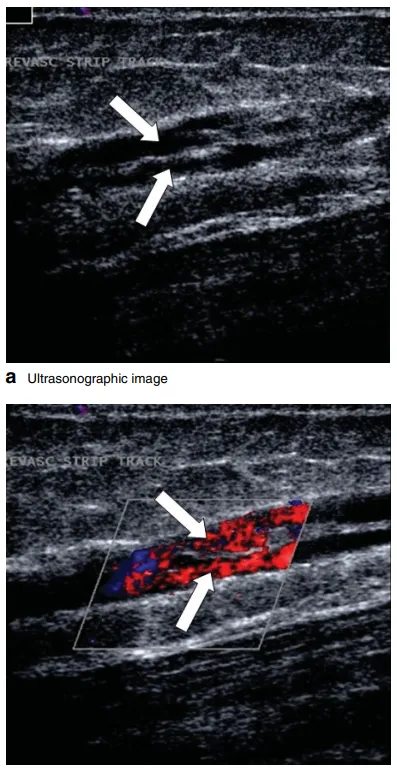

开放手术,高位结扎通常伴有剥除术,仅是EVTA或UGFS之后N2静脉干功能不全的三线推荐治疗方法。这是适当的,因为手术的疼痛和不适,以及已证实的剥除处血管再生,23%的人在1年内出现一些剥除处血管再生,超过80%的人在5-8年内出现一些剥除处血管再生。大量随机对照研究表明,开放手术具有与EVTA相似的结局,这促使一些外科医生根据这些结果继续开展开放手术。

图:a 大隐静脉剥脱术后1年大腿剥除处血管再生的纵向超声图像。注意存在多个管道。b 彩色血流多普勒图像显示剥除处血管再生大腿上每个管道都有反流。

图:大隐静脉剥脱术后1年大腿血管再生的横向超声图像,四个管道可见。